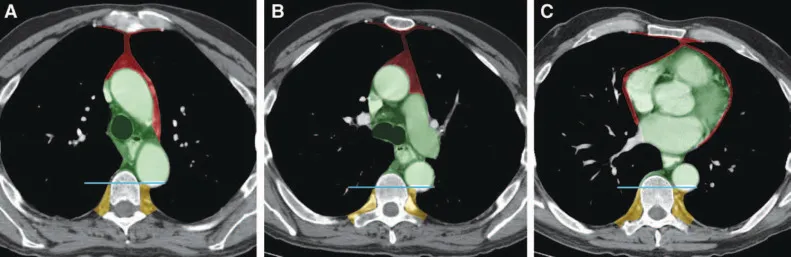

- Divided by transverse thoracic plane (sternal angle of Louis to T4-T5 IV disc).

- Superior Mediastinum: Above this plane.

- Inferior Mediastinum: Below this plane; subdivided.

- Anterior: Sternum to pericardium. Contents: Thymus remnants, lymph nodes, fat.

- Middle: Contains pericardium & heart. Contents: Heart, great vessel roots (ascending aorta, pulm. trunk, SVC), phrenic nerves.

- Posterior: Pericardium to vertebrae (T5-T12). Contents: Esophagus, descending aorta, azygos/hemiazygos veins, thoracic duct.